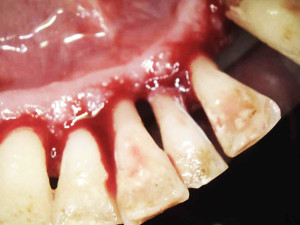

Na pierwszej wizycie usunięto złogi kamienia nad- i poddziąsłowego za pomocą skalera ultradźwiękowego EMS oraz osady i biofilm za pomocą piaskarki airflow S2 EMS –użyto piasku AIR-Flow PLUS. Ponieważ pani jest bardzo wrażliwą osobą, a stan zapalny dziąseł był bardzo duży, pacjentka została miejscowo znieczulona do zabiegu.

Na drugiej wizycie przeprowadzono dokładną kontrolę pozabiegową. Oznaczono ponownie wszystkie wskaźniki notując znaczną poprawę – API 17%, PBI 33%, sprawdzono głębokość kieszonek i ruchomości zębów.